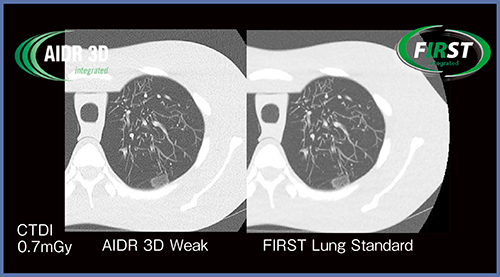

当院では,医師の要望に基づき肺野条件ではAIDR 3D Weakを用いてFBPに近い画像を提供しているが,FIRSTを適応した場合の評価を,背側側に−700HUのすりガラス陰影(GGO)を模擬した腫瘤のあるファントムを用いて行った。

図3は,通常線量の約1/10に当たるCTDI:0.7mGyで撮影した画像だが,シャープさはAIDR 3D Weakの方がやや優位であるものの,描出能はFIRSTの方が有効と考えられる。

図3 低線量肺がんCTにおけるAIDR 3DとFIRSTの比較